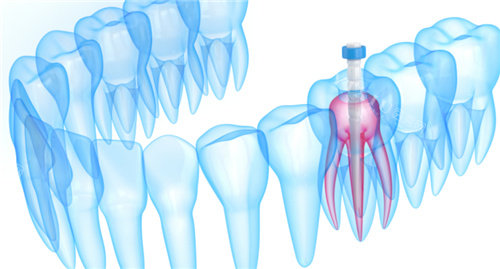

乳牙磨牙根管治疗:1080 元起

抽牙髓治疗:900 - 1000 元起